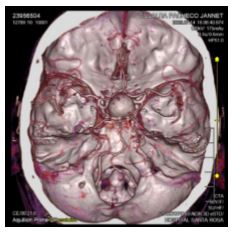

Imaging tests: CT scans revealed a saccular aneurysm of the right supraclinoid internal carotid artery associated with bone remodeling (Figures 1 and 2). On the other hand, magnetic resonance imaging (MRI) of the pituitary showed a saccular aneurysmal dilation occupying the sella turcica with suprasellar extension, originating from the right internal carotid artery.

Figure 2. CT angiographic reconstruction of the brain. Approximate measurements of 20.6 x 1.6 x 16.7 mm in the anteroposterior, transverse and craniocaudal dimensions, with involvement of the sella turcica and originating from the right internal carotid artery.